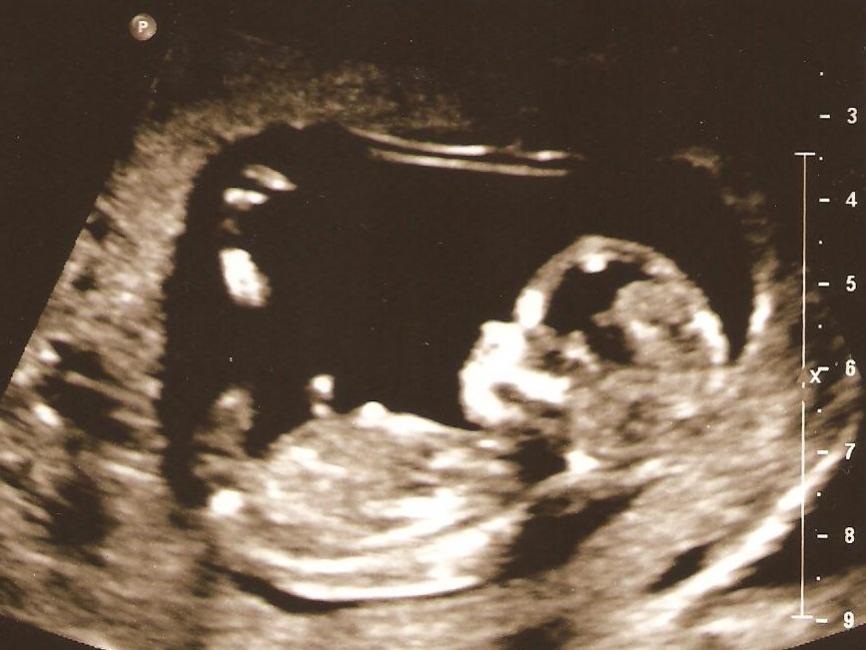

Yikes, haven't posted on here in awhile! Gave up on swaying for a girl in June since this is my first and decided to see what #1 would be before swaying for the next. I got pregnant at the end of July and just had my 13 week NT scan. What do you all think?!?! I'm thinking girl, but not sure. Any guesses would be appreciated!

Attachment 654